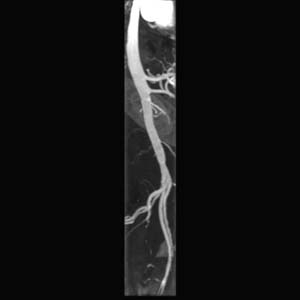

RADIOLOGY: VASCULAR: Case# 34160: MRA.